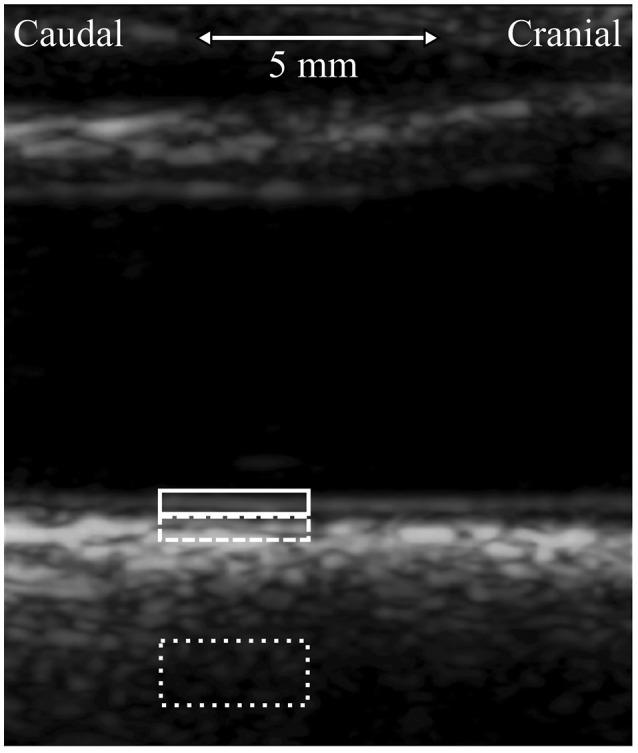

The longitudinal motion of the carotid wall is a potential new measure of arterial stiffness. Despite the over decade long research on the subject, the driving force and the specific longitudinal kinetics of the carotid wall has remained unclear. In this study, a transfer function analysis with 20 healthy subjects is presented to derive how the energy from the blood pressure moves the innermost arterial wall longitudinally and how the kinetic energy is then transferred to the outermost arterial layer. The power spectrums display that the main kinetic energy of the longitudinal motion is on band 0-3 Hz with a peak on the 1.1 Hz frequency. There is a large variation among the individuals, how the energy from the blood pressure transfers into the longitudinal motion of the arterial wall since the main direction of the longitudinal motion varies individually and because early arterial stiffening potentially has an effect on the time characteristics of the energy transfer. The energy transfer from the innermost to the outermost wall layer is more straightforward: on average, a 17% of the longitudinal amplitude is lost and an 18.9 ms delay is visible on the 1.0 Hz frequency.

颈动脉壁的纵向运动是一种潜在的动脉僵硬度新测量指标。尽管对该主题进行了长达十多年的研究,但颈动脉壁的驱动力和具体纵向动力学仍不清楚。在本研究中,对20名健康受试者进行了传递函数分析,以推导血压能量如何纵向移动最内层动脉壁,以及动能随后如何传递到最外层动脉层。功率谱显示,纵向运动的主要动能在0 - 3 Hz频段,在1.1 Hz频率处有一个峰值。个体之间存在很大差异,因为纵向运动的主要方向因人而异,且早期动脉僵硬度可能对能量传递的时间特征有影响,所以血压能量如何转化为动脉壁的纵向运动存在差异。从最内层到最外层壁层的能量传递更为直接:平均而言,纵向振幅损失17%,在1.0 Hz频率处可见18.9毫秒的延迟。